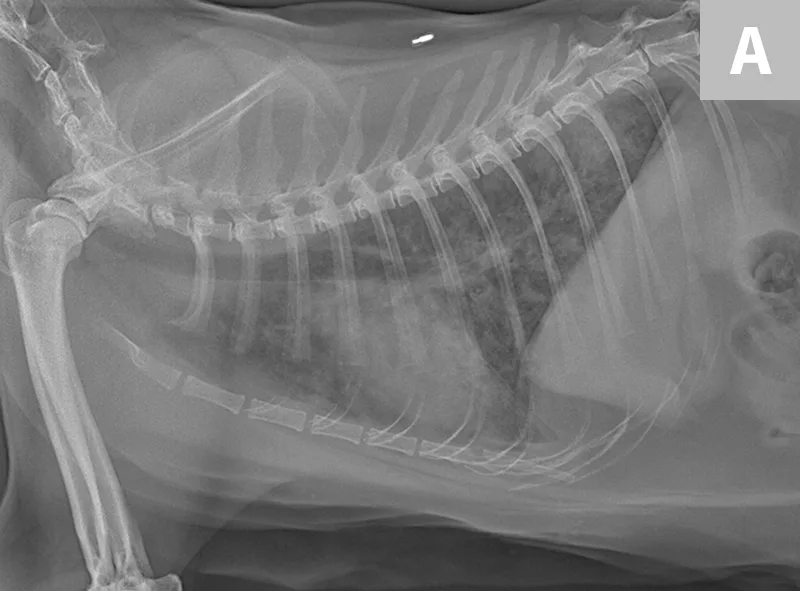

Radiographs of the thorax revealed a diffuse, finely granular interstitial pulmonary infiltrate with prominent bronchial markings with indistinct nodules in the middle and caudal lung lobes (Figure 2).

Figure 2

Diffuse, finely granular interstitial pulmonary infiltrate (A) with prominent bronchial markings with indistinct nodules in the middle and caudal lung lobes (B)